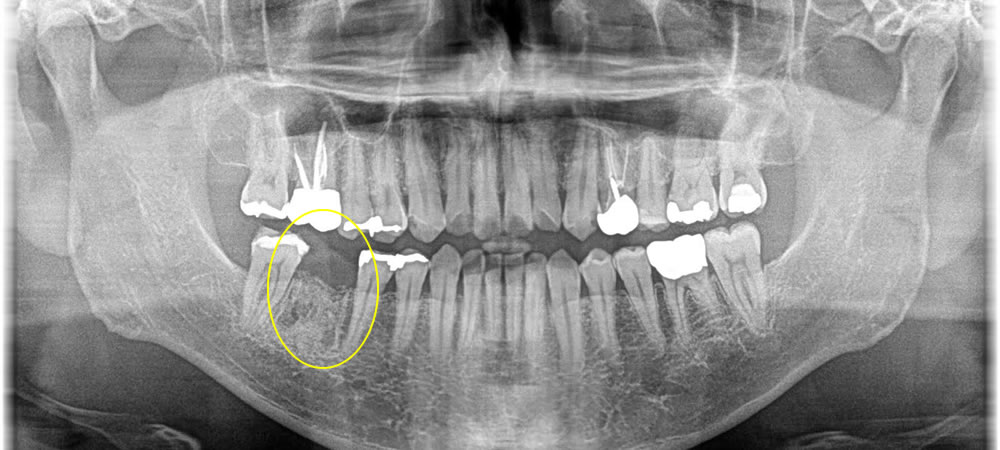

昔に根の治療を行っている歯に感染が起き、痛みが強く出ているという主訴で来院された患者さまです。患者さまと相談し、当該歯を抜歯してインプラントで治療する計画を立てました。

当該歯の下顎の骨の中には太い神経が近くにあるので、まず歯を抜いて骨を増やす処置だけを行った後、3ヵ月待ってからインプラントを埋入していきました。